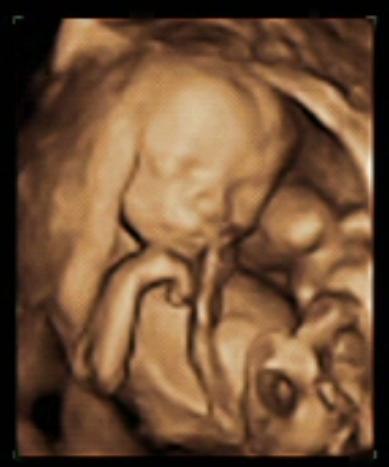

rzadko tu do was zaglądam ostatnio... nawet nie wiem, czy wątek, który wybrałam jest aktualnie najodpowiedniejszy na tego typu posty... w każdym razie chciałam Wam przedstawić szybciutko Antośkowego Braciszka